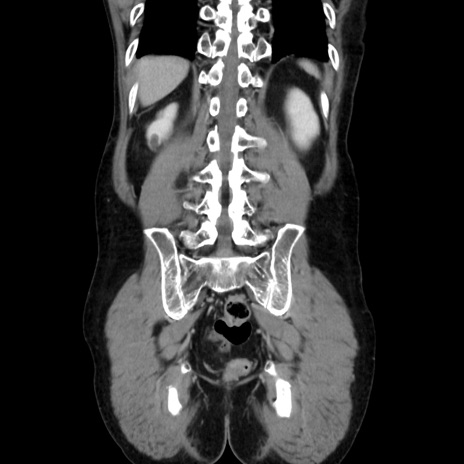

横断像